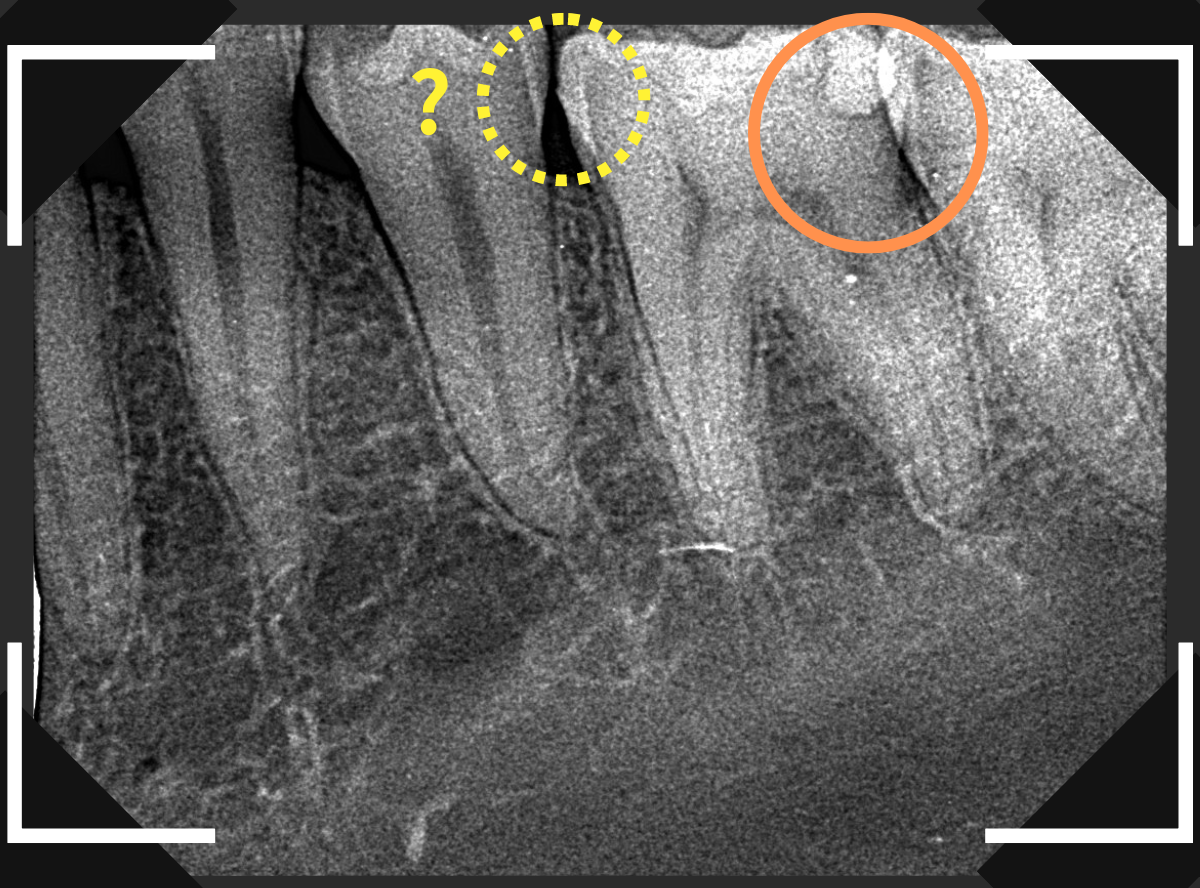

Case.5 レジンの中の虫歯がよくわからない

「奥歯に違和感がある」という訴えの患者さんのケースです。

黄色い丸の部分、レジンが明らかに劣化して中が黒く透けて虫歯になっていそうです。

レントゲン写真で確認します。

レントゲンでは、黄色い丸の部分は虫歯ではなさそうに見えます。

逆に反対側のオレンジ色の丸の部分にレジンがつまっていて、中で虫歯になっていそうなのはわかります。

あとは、レジンを除去して中を調べてみるしかありません。

レジンを除去してみました。

やはり中で虫歯が進行していました。

前後の歯にまで虫歯が広がっています。

全ての虫歯を除去しました。

かなり広範囲な虫歯でした。

今回は、見た目から虫歯がある診断がつきましたが、より診断がつきづらいケースもあり、そういった虫歯を突き止めるには、ドクターの経験と患者さんとの信頼関係が必要です。